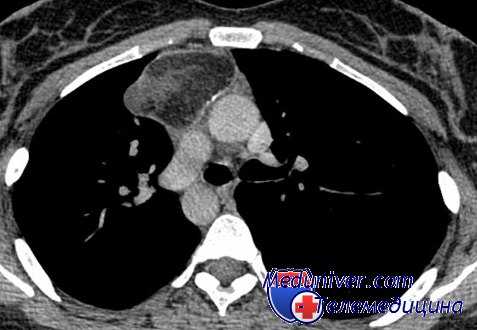

Рентгенологическое исследование: срединная тень почти на всем своем протяжении расширена в обе стороны за счет патологического затемнения, занимающего большую часть переднего средостения. Это интенсивное, неоднородное затемнение имеет дольчатую форму с бугристыми четкими контурами, расположенными местами (справа) в виде «кулис». На жестком снимке с передержкой и на томограммах более отчетливо выявляется дольчатый характер патологического образования и узлы, расположенные на различной глубине, видны также неизмененные трахея и главные бронхи. Пищевод не изменен.

Очаговых и инфильтративных изменений в легких не определяется. Куполы диафрагмы подвижны, синусы свободны. Корни легких, сердце и аорта не определяются из-за наложения на них описанного затемнения.